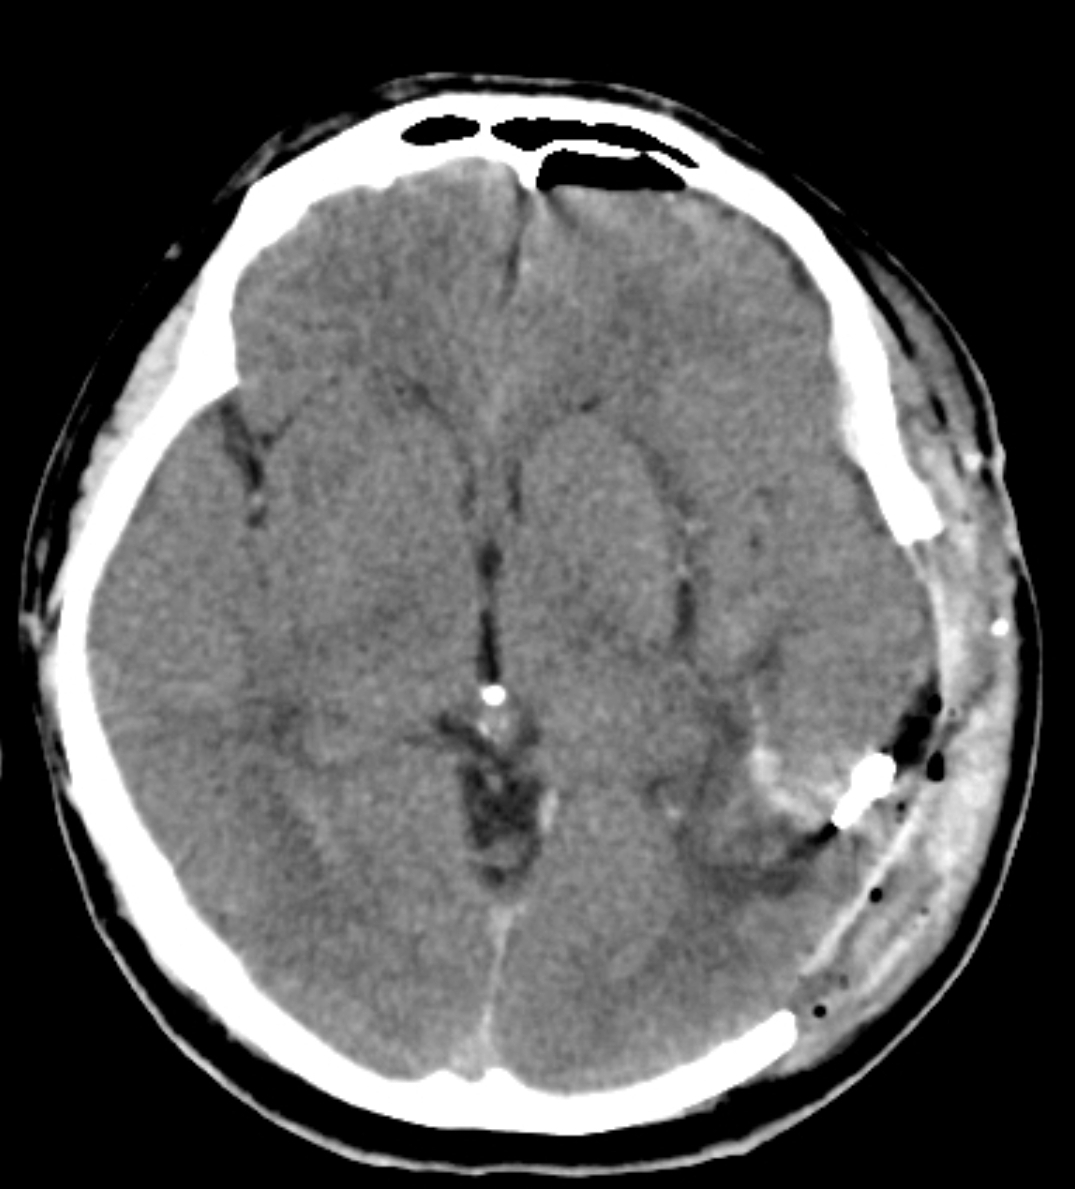

患者,男性39岁。上班时突发昏迷1小时急诊入院。查体:神志昏迷,双瞳散大,光反射消失。

急诊头部CT显示左颞顶巨大脑内血肿,中线结构移位,脑疝